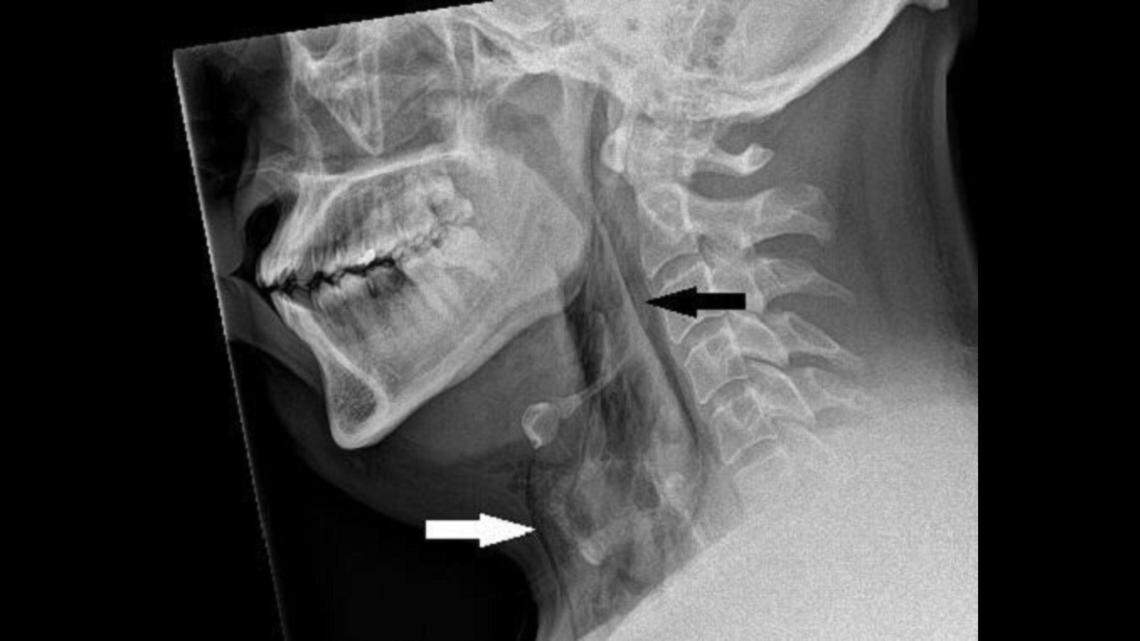

The stifled sneeze tore through the lining of the man’s trachea, doctor’s said, as seen on X-ray marked by the black arrow.

The stifled sneeze tore through the lining of the man’s trachea, doctor’s said, as seen on X-ray marked by the black arrow. BMJ Case Reports

The air shot into his trachea, or windpipe, and ripped through the soft tissue, according to the case report, creating a tear in the lining.